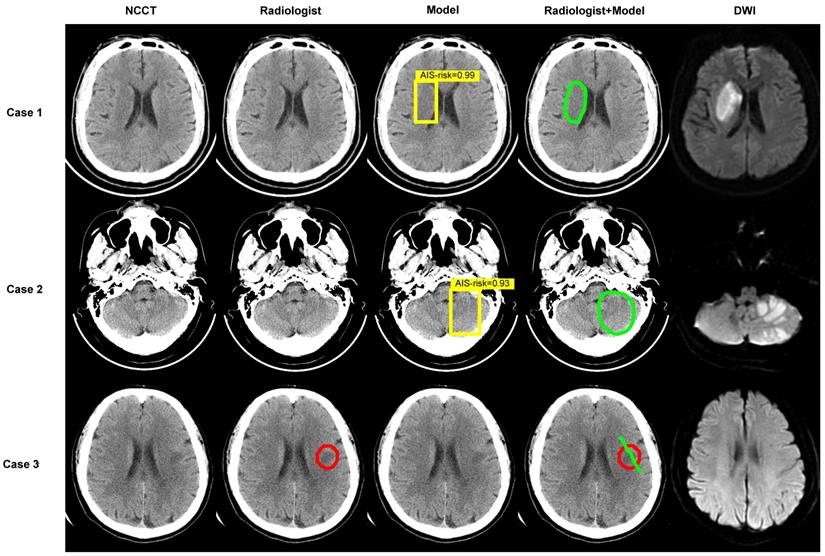

Figure 4

Examples. Images show the results of two experienced radiologists without and with the assistance of the deep-learning model for diagnosing. The first two cases are AIS patients and the last was imaging-negative patient. Within each case, left column shows a NCCT image, second column shows the result of radiologist read, middle column shows result of model diagnose (the yellow box represents the location of AIS and the probabilities calculated by the model in this region are 0.99, 0.93), fourth column shows the result of “radiologist + model” (the green circle or line), and right column shows corresponding DWI.

We performed analyses by converting the slices into patients. In accordance with the rules, when at least one AIS NCCT slice was detected, the AIS patient was recorded as true positive. In patients with negative imaging, the absence of lesions in all slices was considered true negative. Table 3 shows an AUC of 62.02% (95% CI: 54.20-69.84%), 63.51% sensitivity (95% CI: 52.67-74.32%), 60.53% specificity (95% CI: 48.68-71.05%), and 62.00% accuracy (95% CI: 53.72-69.79%) without the model and 92.07% AUC (95% CI: 87.82-96.32%), 97.30% sensitivity (95% CI: 93.24-100.00%), 86.84% specificity (95% CI: 78.95-93.42 %), and 92.00% accuracy (95% CI: 86.44-95.08%) with the model for radiologist 1. For radiologist 2, the reported values were 58.71% AUC (95% CI: 50.80-66.62%), 62.16% sensitivity (95% CI: 51.35-72.97%), 55.26% specificity (95% CI: 44.74-67.11%), and 58.67% accuracy (95% CI: 50.35-66.64%) without the model and 84.83% AUC (95% CI: 79.44-90.22%), 97.30% sensitivity (95% CI: 93.24-100%), 72.37% specificity (95% CI: 61.84-81.58%), and 84.67% accuracy (95% CI: 77.89-90.02%) with the model. The AUCs achieved by radiologists with the assistance of the model showed greater predictive performance than without the model (P < 0.001) (Figure 3C). Besides, sensitivity, specificity, and accuracy by radiologists with the assistance of the model were higher than those without the model (P < 0.001) (Figure 3E, Table S2). Of 150 patients, the number diagnosed correctly increased by 45 (radiologist 1) and 39 (radiologist 2) while using the deep-learning model. Figure 4 displays three examples without and with the assistance of the model reported by radiologists.